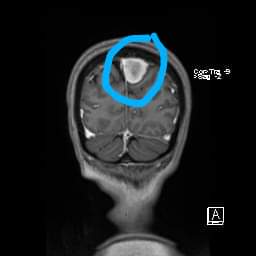

For those who don't know, this is a picture of my wife's brain. This thing has been there for at least 9 years and the ONLY treatment available has been cannabis. It's barely grown in that time, less than 1 mm/year ✌️💚🪴 #CannabisCures #CannabisCommunity #CannaLand